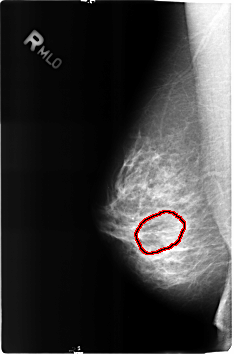

FILE: B_3160_1.RIGHT_MLO.OVERLAY

TOTAL_ABNORMALITIES 1

ABNORMALITY 1

LESION_TYPE MASS SHAPE OVAL MARGINS N/A

ASSESSMENT 2

SUBTLETY 3

PATHOLOGY BENIGN

TOTAL_OUTLINES 1

BOUNDARY